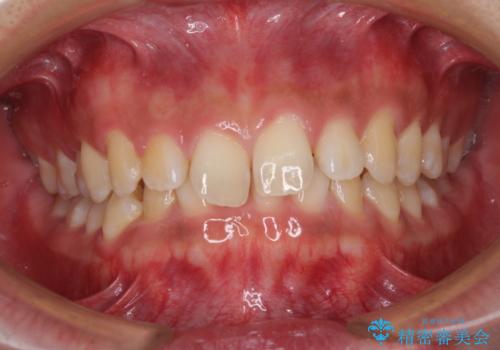

軽微叢生をインビザラインで 廉価版パッケージでの矯正治療

早くて安くて楽ちん メタルブラケットでの矯正治療

前歯のがたつき 深い噛み合わせを改善したい